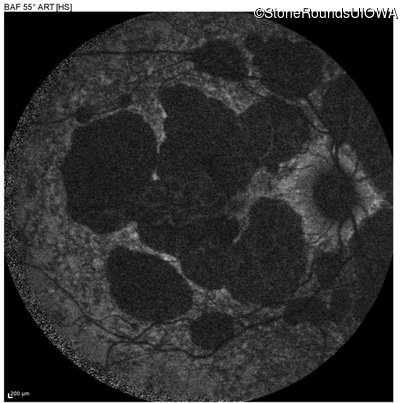

AR Stargardt Disease (IIA)

Age at visit: 51 years

This 51 year old woman first experienced some abnormality in her distance vision when she was 27 years old. She feels that her vision has been stable since that time.

Diagnosis & molecular findings

Disease Gene Allele 1 variant(s) Allele 2 variant(s) Inheritance mode

AR Stargardt Disease ABCA4 Gly1507Arg GGG>AGG IVS42+1 G>A AR